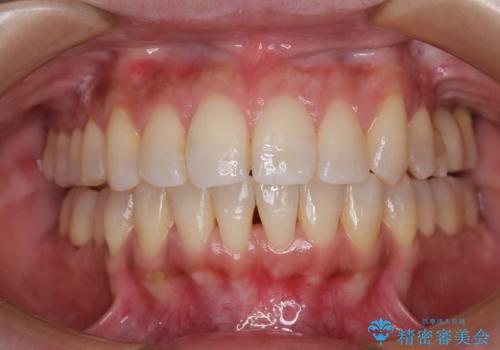

インビザラインによる矯正治療と奥歯のインプラント治療

- 全体的なデコボコと、以前抜歯した歯のスペースを閉じた部分が気になるとのことで来院された患者様です。

左上第一大臼歯を抜歯した際に、スペースを閉じたそうですが、歯が傾斜してものが挟まって不快とのことでした。

インビザライン矯正で全体の歯列と整えるとともに、左上第一大臼歯部にはスペースを作り、インプラントによる補綴治療を行うこととしました。

歯の傾斜が改善され、インプラントによるクラウンが装着されたことで、物が挟まることもなくなりました。